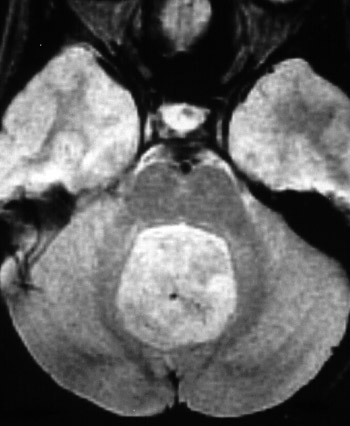

The axial MRI scan above and the enhanced MR scan below demonstrate a medulloblastoma in a child. These tumors tend to occur in the cerebellar vermis, with a peak incidence in the first two decades of life.